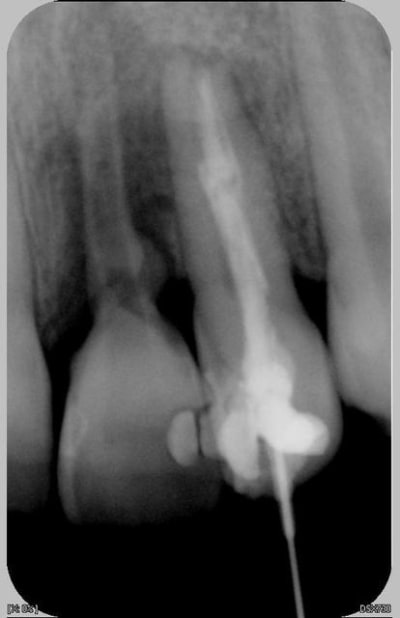

Patiente de 11 ans ayant la 21 expulsée début avril 2006. La dent a été repositionnée en centre de soins. Dans un premier temps, pas de perte de sensibilité. Puis dans un deuxième temps, comme un goût de ça tourne mal avec certainement rhyzalyse interne de la 22 (traitement thermafil pas d'école).

la on est dans un tres beau cas de resorption inflammatoire des 21 et 22

pour la 21,ne pas toucher au fantome de racine qui reste,il va disparaitre

la 22 :evident,reprise du traitement endo

Le milieu est extémement infecté et la résorbtion de la 21 n'est pas aseptique : donc je ne peux pas attendre.

Mon collègue en mon absence a essayé de traiter la 22 et mis un composite pour éviter l'expulsion de la 21. Souvent on fait comme on peut et je sens que la critique va fuser tel la pierre qui ricoche. que celui qui n'a fait que des traitements de rêve la lance.

Ci joint la première radio de ces dents avec attelles centre de soins universitaire